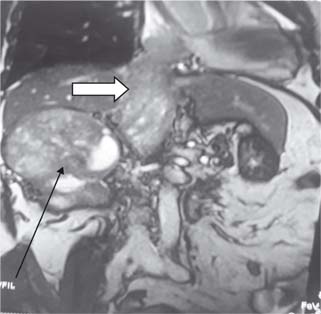

The surgical technique used for different levels of thrombus extension in our study is as follows. For level I (Figure 1) thrombus, vascular side clamps are used without occluding IVC inflow. The cavotomy defect is then sewn using a continuous prolene 4-0 suture. Level II thrombus (Figure 2A and B) often necessitates more extensive mobilization of the IVC. Proximal and distal control of IVC is necessary with ligation and division of lumbar veins to prevent significant blood loss. For the retrieval of thrombus, vascular clamps are used with clamping of the left renal vein in case of right-sided renal tumors and clamping of the right renal artery in case of left-sided renal tumors. The cavotomy defect is sewn using continuous prolene 4-0 suture. For level IV thrombi (Figure 3), a beating heart surgery with a simplified CPB technique was used for retrieval of thrombus from RA. For level IV thrombi, ligation of renal artery is followed by radical nephrectomy using chevron incision. The left renal vein is looped, and IVC below the renal vein is skeletonized for a length of about 5 cm to prepare it for IVC cannulation. A purse string is made on it using 4-0 prolene monofilament suture and the subhepatic portion of IVC is dissected. Then, median sternotomy is performed and pericardium is opened. Aortic purse-string suture with 3-0 prolene is taken on the ascending aorta. The intrapericardial portion of the superior vena cava (SVC) is looped, and a purse-string with 3-0 prolene is taken. Patient is heparinized with 300 Units/kg body weight of heparin. Aortic and venous cannulations are performed, and patient is put on complete CPB after both SVC and IVC are snugged with Rummel tourniquet. No vent cannula is put in. Patient is cooled to 35°C. On beating heart under normothermic CPB, RA thrombus (Figure 4) is extracted without cross-clamping the aorta. Right atriotomy is performed and tumor thrombus, which is organized and firm, is carefully retrieved. IVC is snugged at its junction with RA to prevent spillover from IVC into RA. Subhepatic IVC is incised longitudinally, and the tumor thrombus is extracted, using digital manipulation to ensure complete removal from retrohepatic IVC. Intermittent suctioning is performed using a pump sucker as hepatic veins are opened up. Cavotomy is closed using 4-0 prolene suture. After completely de-airing the RA, the atriotomy is also closed. Patient is gradually weaned off the bypass. “Patients were followed up quarterly in the first year, semiannually in the second year, and annually thereafter”.

Figure 3: Level 4 thrombus with arrow (Black) showing mass in right kidney and white arrow thrombus in IVC extending to right atrium.